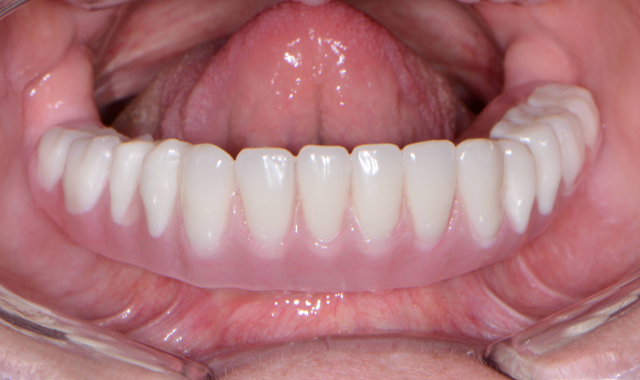

The first step was to brush a thin coat of adhesive into the overdenture recesses (Fig. 14) to enhance retention between the denture base and the hard reline material. Petroleum jelly was applied to the surrounding surfaces of the denture to prevent unwanted adherence of excess material. Once mixed, the Rebase II material (Figs. 15 & 16) was placed into a plastic dispensing syringe and injected up to two-thirds the height of each recess as well as on to the attachments. During seating, the prosthesis was gently held in place by hand. After a total of about three minutes, the overdenture with the incorporated retention caps was removed. Any excess material was removed with a trimming bur (Fig. 17). At the completion of the prosthetic phase, the patient stated how pleased she was to be able to smile and function without the prosthesis wobbling or falling out (Fig. 18). Most importantly from a clinical standpoint, we were pleased to see the areas in the upper and lower arches healthy and infection-free.

Fig. 17 Fig. 18